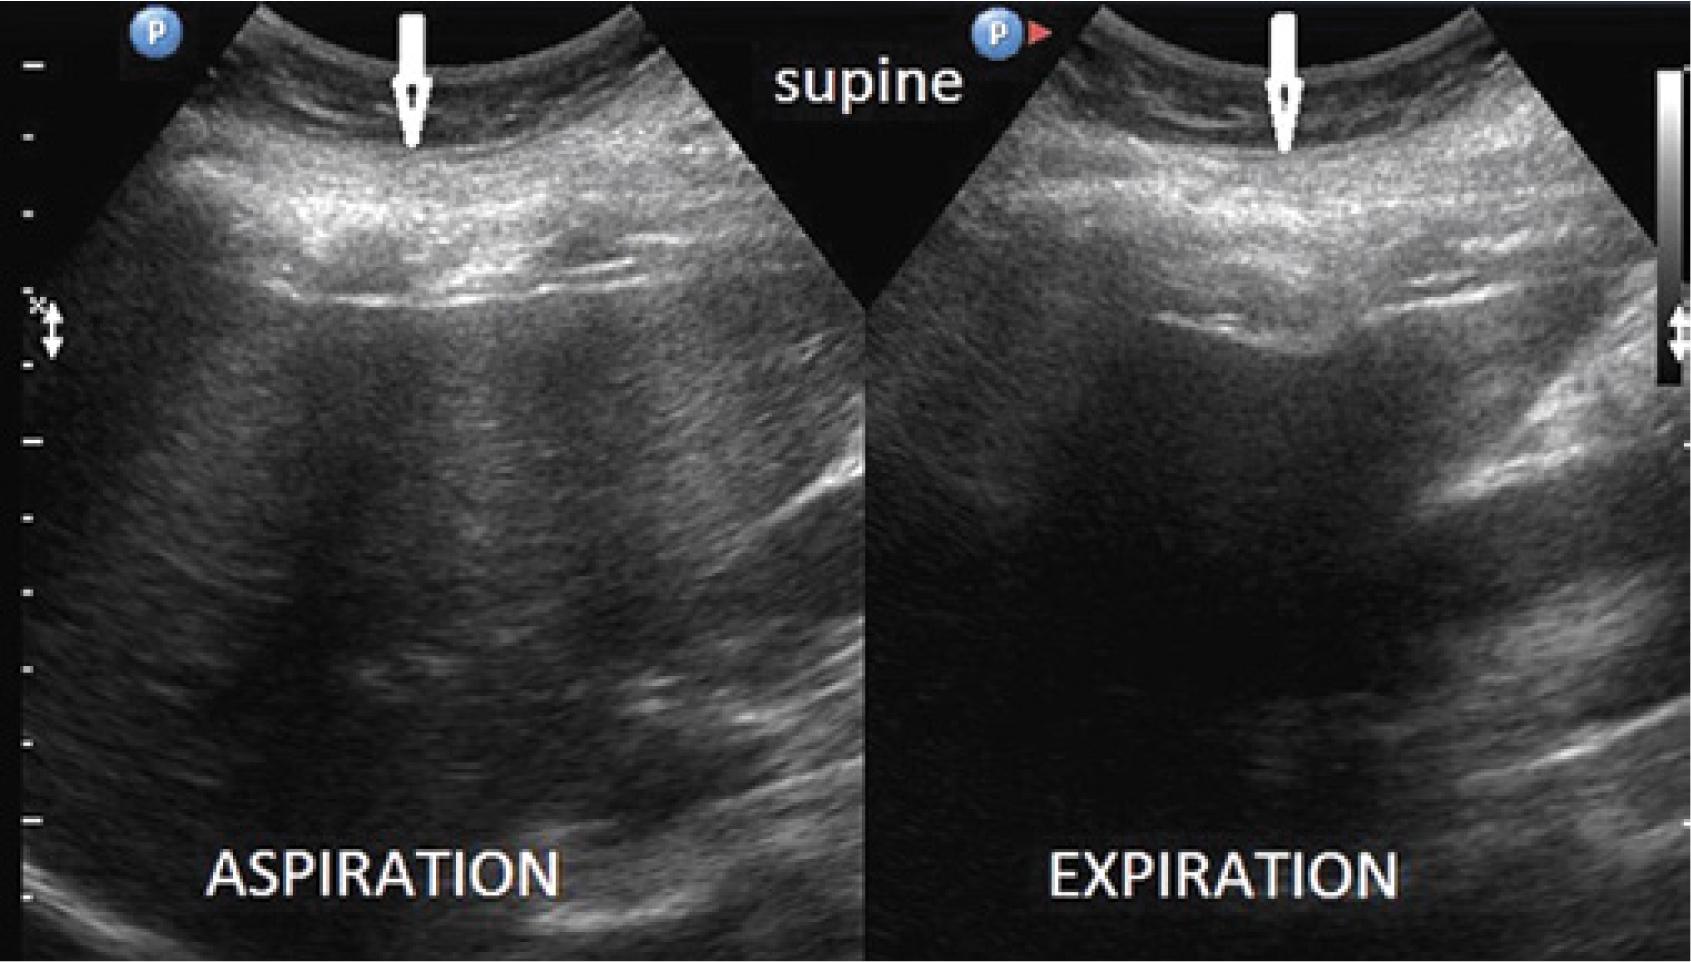

Comparison of the thickness of the musculocartilaginous complex during inhalation, exhalation, supine position, sitting position and forward trunk flexion in 178 patients

| Inhalation | 11–28 mm | 14.5 mm +/− 2.4 | Exhalation | 12–40 mm | 21.5 mm +/− 3.3 |

| Inhalation | 14.5 mm | Exhalation | 21.5 mm |